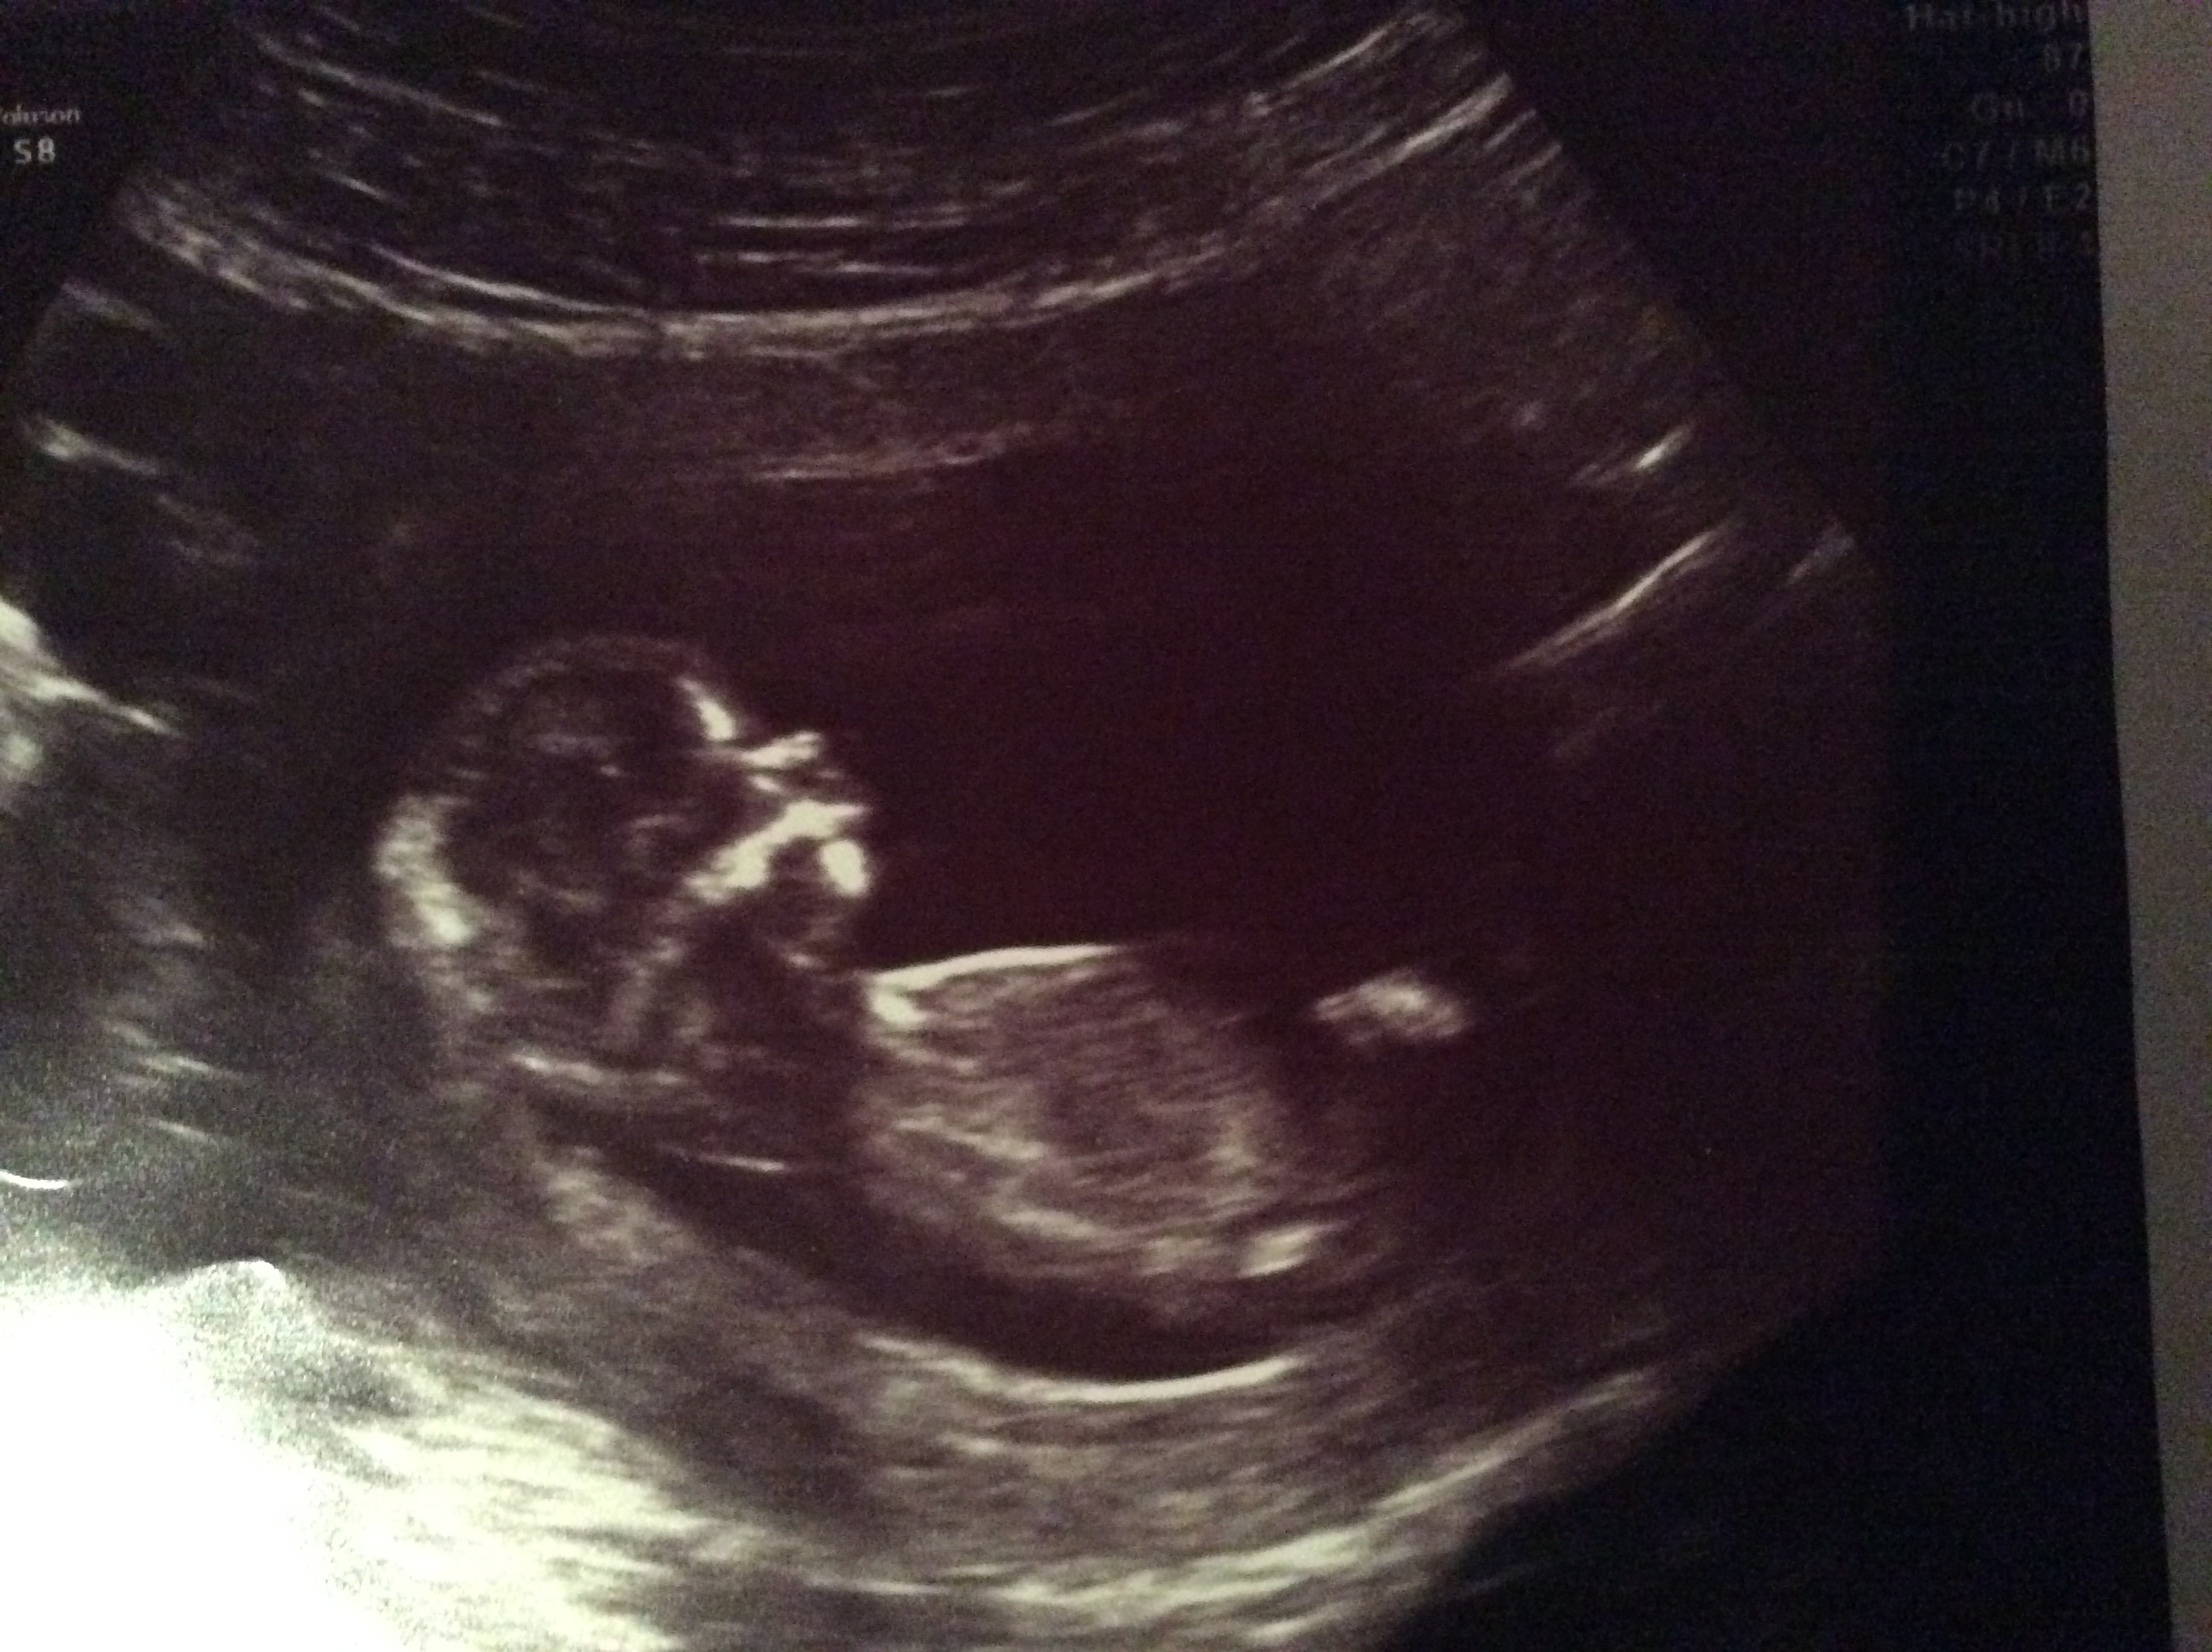

Attachment 28489 Any guesses thank you

I don't see a nub. Sorry hun but congratulations!